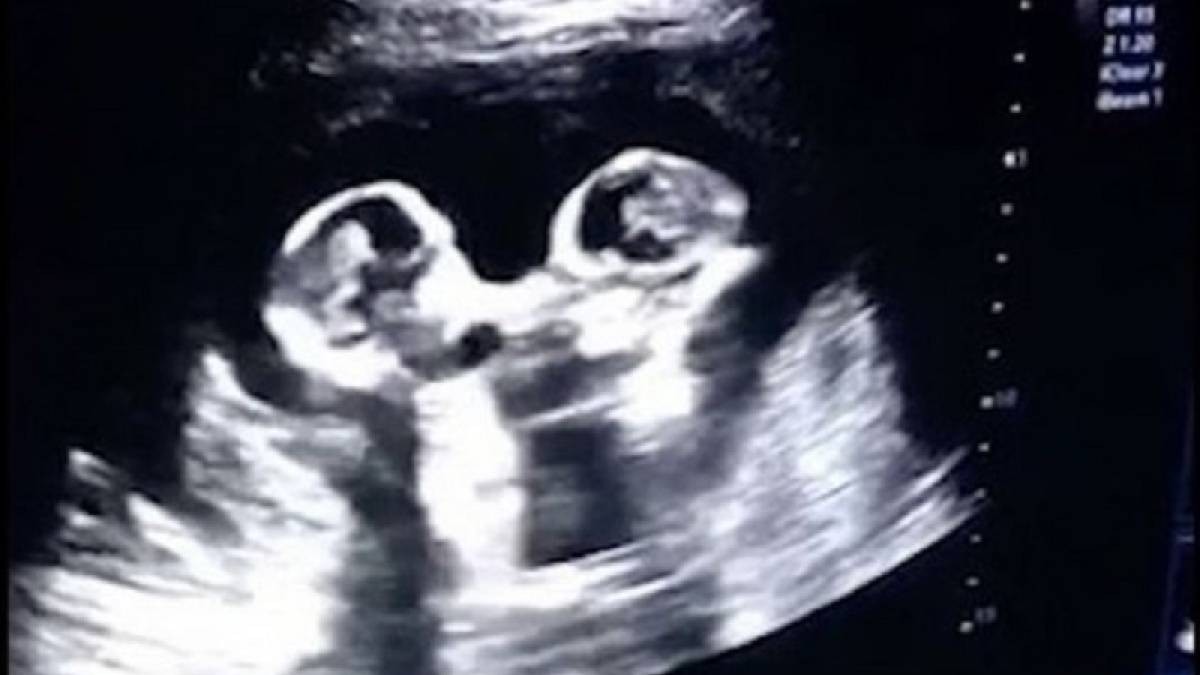

Анасының құрсағынан УКС арқылы түсірілген егіз сәбилердің төбелесі көпшілікті таңғалдырды.

28 жастағы Тао есімді қытайлық азамат жүкті әйелінің құрсағындағы егіз балалардың видесын жариялады. Кадрдан егіз қыздардың бір-бірін жұдырығымен ұрып жатқаны байқалады. Бұл көрініс балалардың әкесін күлкіге қарық қылды.

Ал, дәрігерлер мұның қауіпті екенін айтады. Әдетте егіздер құрсақта өзіндік амниотилық қабында болады. Бұл бір-бірінен бөліп тұрады. Ал, бұл жолы егіздер бір ғана амниотикалық қапта. Бұл сирек кездеседі. Соққыдан екеуі немесе бірі өлі тууы мүмкін. Ондағы негізгі қауіп - бала тыныс алатын кіндіктің қысылып қалуы. Мұндай жағдайда балалардың тірі қалуы 50 пайыз.

Не дегенмен егіз қыздар аман-есен өмірге келді. Екеуі де сау. Бірі 1630, бірі 1950 грамм салмақта.